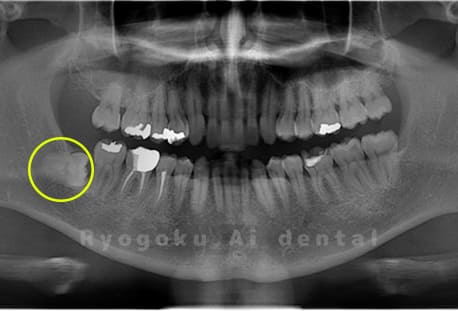

Case03

- 原因

- 上顎、下顎の親知らず

- 治療内容

- 上下4本の親知らずを抜歯したケースです。

<リスク・副作用>

手術後は痛み、腫れ、痺れなどの副作用が生じる場合があります。